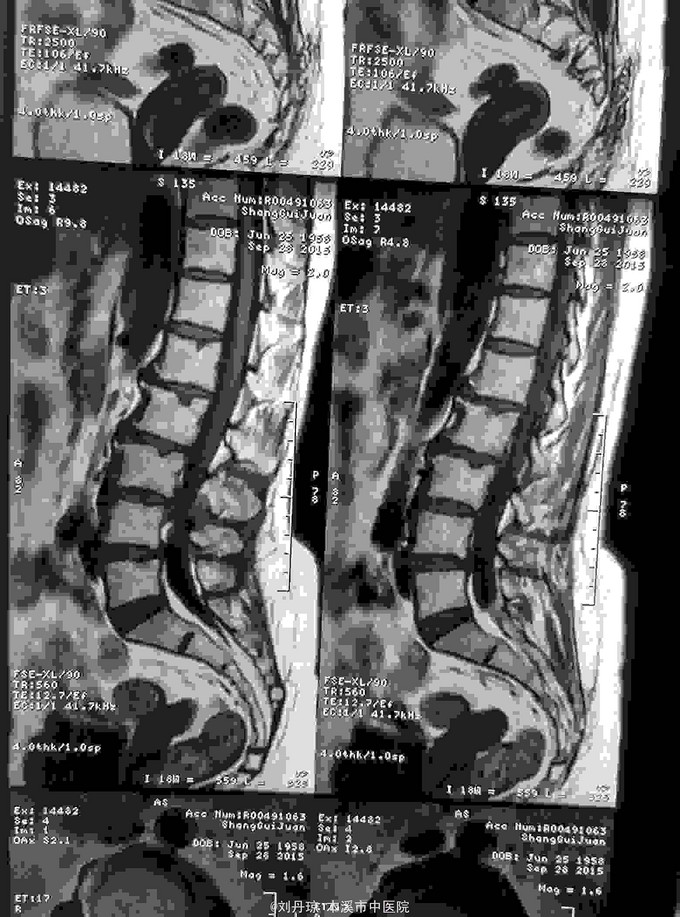

腰部疼痛伴右下肢放射痛麻木感半年,加重2月。患者半年前劳累后感到腰部疼痛伴右下肢放射痛麻木感,近2月病情加重来诊。

查体:L1—S1棘突右旁压痛阳性。直腿抬高实验左70度,右40度。 直腿抬高加强实验左侧阴性,右侧阳性。腰椎功能障碍。 辅查:CT: L1—S1椎间盘突出。

诊断:腰椎间盘突出症 治疗:针灸、雷火灸、中药熏药治疗、小针刀治疗、骶管注射治疗、营养神经药物治疗、脱水药物治疗,当归地黄饮加味。